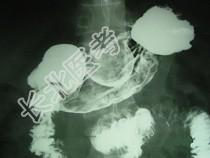

- 单项选择题男,52岁, 中上腹痛,影像检查如图, 最可能的诊断是  (    )

- A、慢性肥厚性胃炎

- B、胃癌

- C、胃溃疡

- D、胃平滑肌瘤

- E、胃平滑肌肉瘤